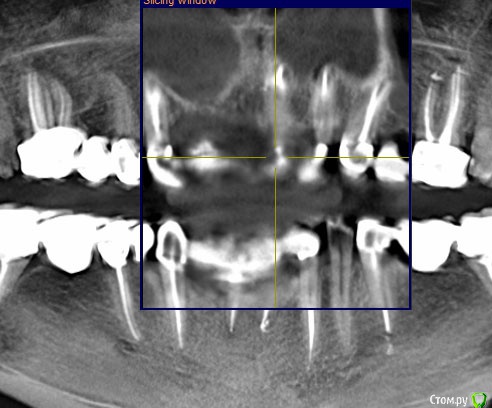

ira. k.. 78 Опубликовано 12 мая, 2020 Поделиться Опубликовано 12 мая, 2020 Здравствуйте уважаемые доктора. Хочу у вас спросить. Зуб клык слева (23), немного стала чувствовать дискомфорт в нем, зуб стоит с штифтом 14 лет, коронку сменила год назад, было всё хорошо, зуб не перелечивали, сделала кт в марте 2020, и увидела у коня немного затемнения, а врач сказал всё хорошо, подскажите, что это, и что с этим делать, мост не хотелось бы снимать, ему только год. Ссылка на комментарий

kramer Опубликовано 12 мая, 2020 Поделиться Опубликовано 12 мая, 2020 Срезы неудачные Ссылка на комментарий

ira. k.. 78 Опубликовано 12 мая, 2020 Автор Поделиться Опубликовано 12 мая, 2020 Здравствуйте, вот такой ещё есть, больше срезов нет Ссылка на комментарий

ira. k.. 78 Опубликовано 12 мая, 2020 Автор Поделиться Опубликовано 12 мая, 2020 Я сама не стоматолог, не знаю как правильно сделать срез Ссылка на комментарий

It'sGeorgy Опубликовано 12 мая, 2020 Поделиться Опубликовано 12 мая, 2020 (изменено) ну если прямо сильно нажимаю на него то ощющение небольшой боли вроде есть, а так кушать не больно им, а что скажите по кт, я в срезах не понимаюНа КТ, действительно, есть очаг разрежения костной ткани вокруг этого зуба. При этом, сказать, что каналы запломбированы плохо - тоже нельзя. Я не терапевт, но со своей точки зрения вижу ситуацию так, что у зуба, на самой вершине, есть достаточно выраженный изгиб, что создало огромную трудность для доктора, который зуб лечил. Этот изгиб, к сожалению, запломбировать ко конца не получилось, что привело к развитию хронического воспаления.Повторюсь, я подобным лечением не занимаюсь и мое мнение может быть ошибочным. Поэтому, предлагаю подождать, пока вам ответит кто-то из здешних терапевтов. это не может быть от зуба?Такие ситуации могут быть от зуба, но тогда боль острая и постоянная. Плюс, тогда пациент сам может определить, что его беспокоит конкретный зуб. В вашем случае, как я понимаю, такого нет. Да и судя по снимку, остальные верхние зубы слева в порядке. делала кт 3 раза за годЕсли есть возможность, выкладывайте их тоже. Потому, что на снимке, который вы выложили очень много фоновых шумов, которые создают металлические конструкции во рту(мостовидные протезы). Возможно, по снимкам до изготовления постоянных конструкций будет видно и понятно лучше. Изменено 12 мая, 2020 пользователем It'sGeorgy Ссылка на комментарий